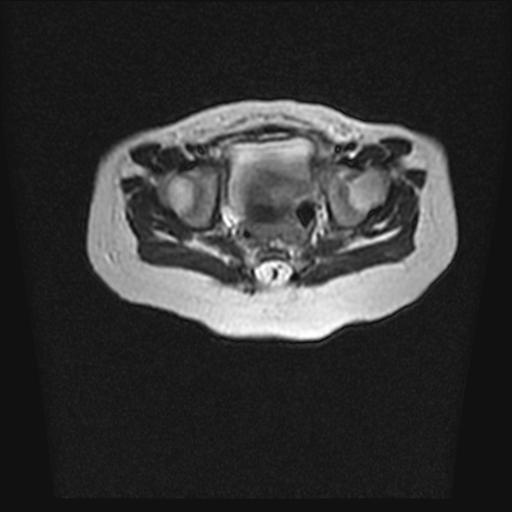

标题: PED0016:脊膜膨出 [打印本页]

标题: PED0016:脊膜膨出

四个月的女婴,ct示脊膜膨出.

脊柱裂、脊膜膨出,请结合临床除外皮毛窦。

脂肪脊髓脊膜膨出

脊柱裂、脊膜膨出